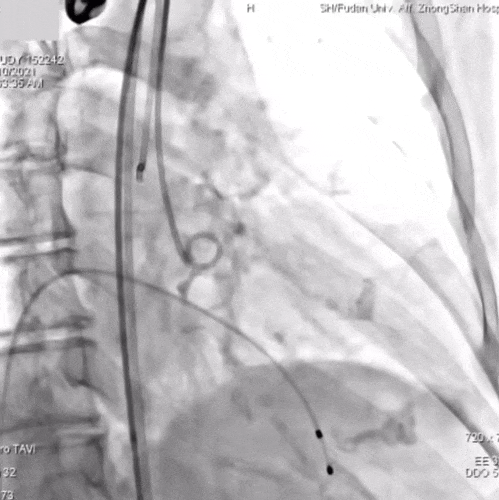

TaurusNXT植入过程:

瓣膜再次定位与展开